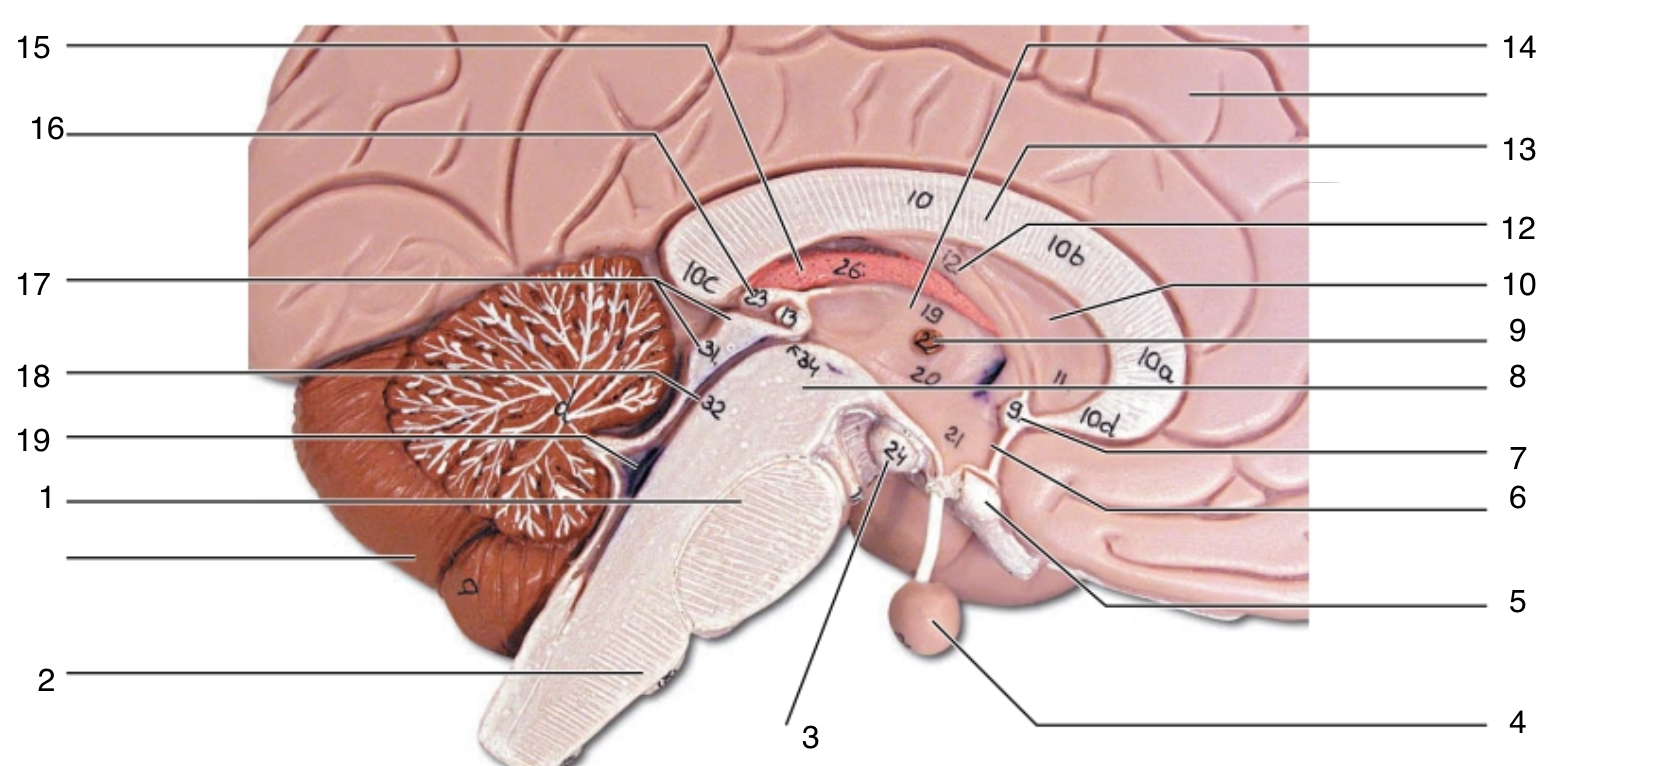

Brain Stem

20 Terms

1

pons

2

medulla oblongata

3

mammillary body

4

pituitary gland

5

optic chiasma

6

hypothalamus

7

anterior commissure

8

midbrain

9

interthalamic adhesion

10

septum pellucidum